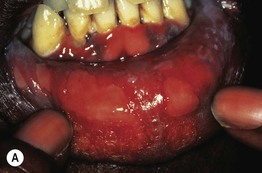

• One or more ulcers, usually anogenital, characterize primary syphilis and are referred to as chancres (Fig. 69.2); the ulcers are painless (unless secondarily infected) and upon palpation the base is firm; regional lymphadenopathy may be present (Fig. 69.3).

Fig. 69.2 Chancres of primary syphilis. The lesions are firm to palpation and are occasionally multiple. Sites of chancres include the penis (A, B), perianal area (C), and lip (D), as well as the fingers, cervix, and breast. A, C, D, Courtesy, Angelika Stary, MD.